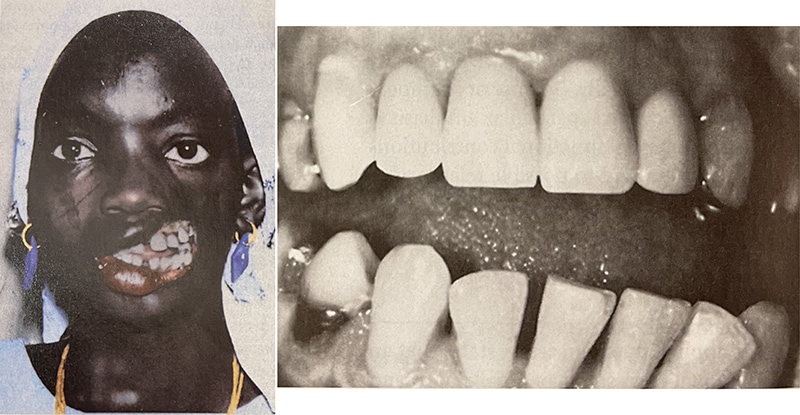

再來看一個比較的極端的案例。下圖中的這位婦女因為臉部受到感染而失去了左側的臉頰,大家就可以很明確地看到所有的牙齒,因為失去臉頰軟組織所提供輕微持續的壓力而導致力不平衡,所以所有的牙齒就會往外傾斜飄移,而主要的推力應該就是口內的舌頭。

由此可知,力的平衡一旦少了外側力,牙齒就會往外;反之少了內側力則會往內推擠,造成牙弓狹窄,而當牙弓變成V字型時,門牙就容易外飛。

下圖的病例主要是被舌頭推擠所造成門牙前飛,甚至出現漏財牙縫。而患者的上下顎骨位置正常,所以主要是齒性的暴牙,看起來很飛但其實治療難度低,大約14個月就順利完成治療。